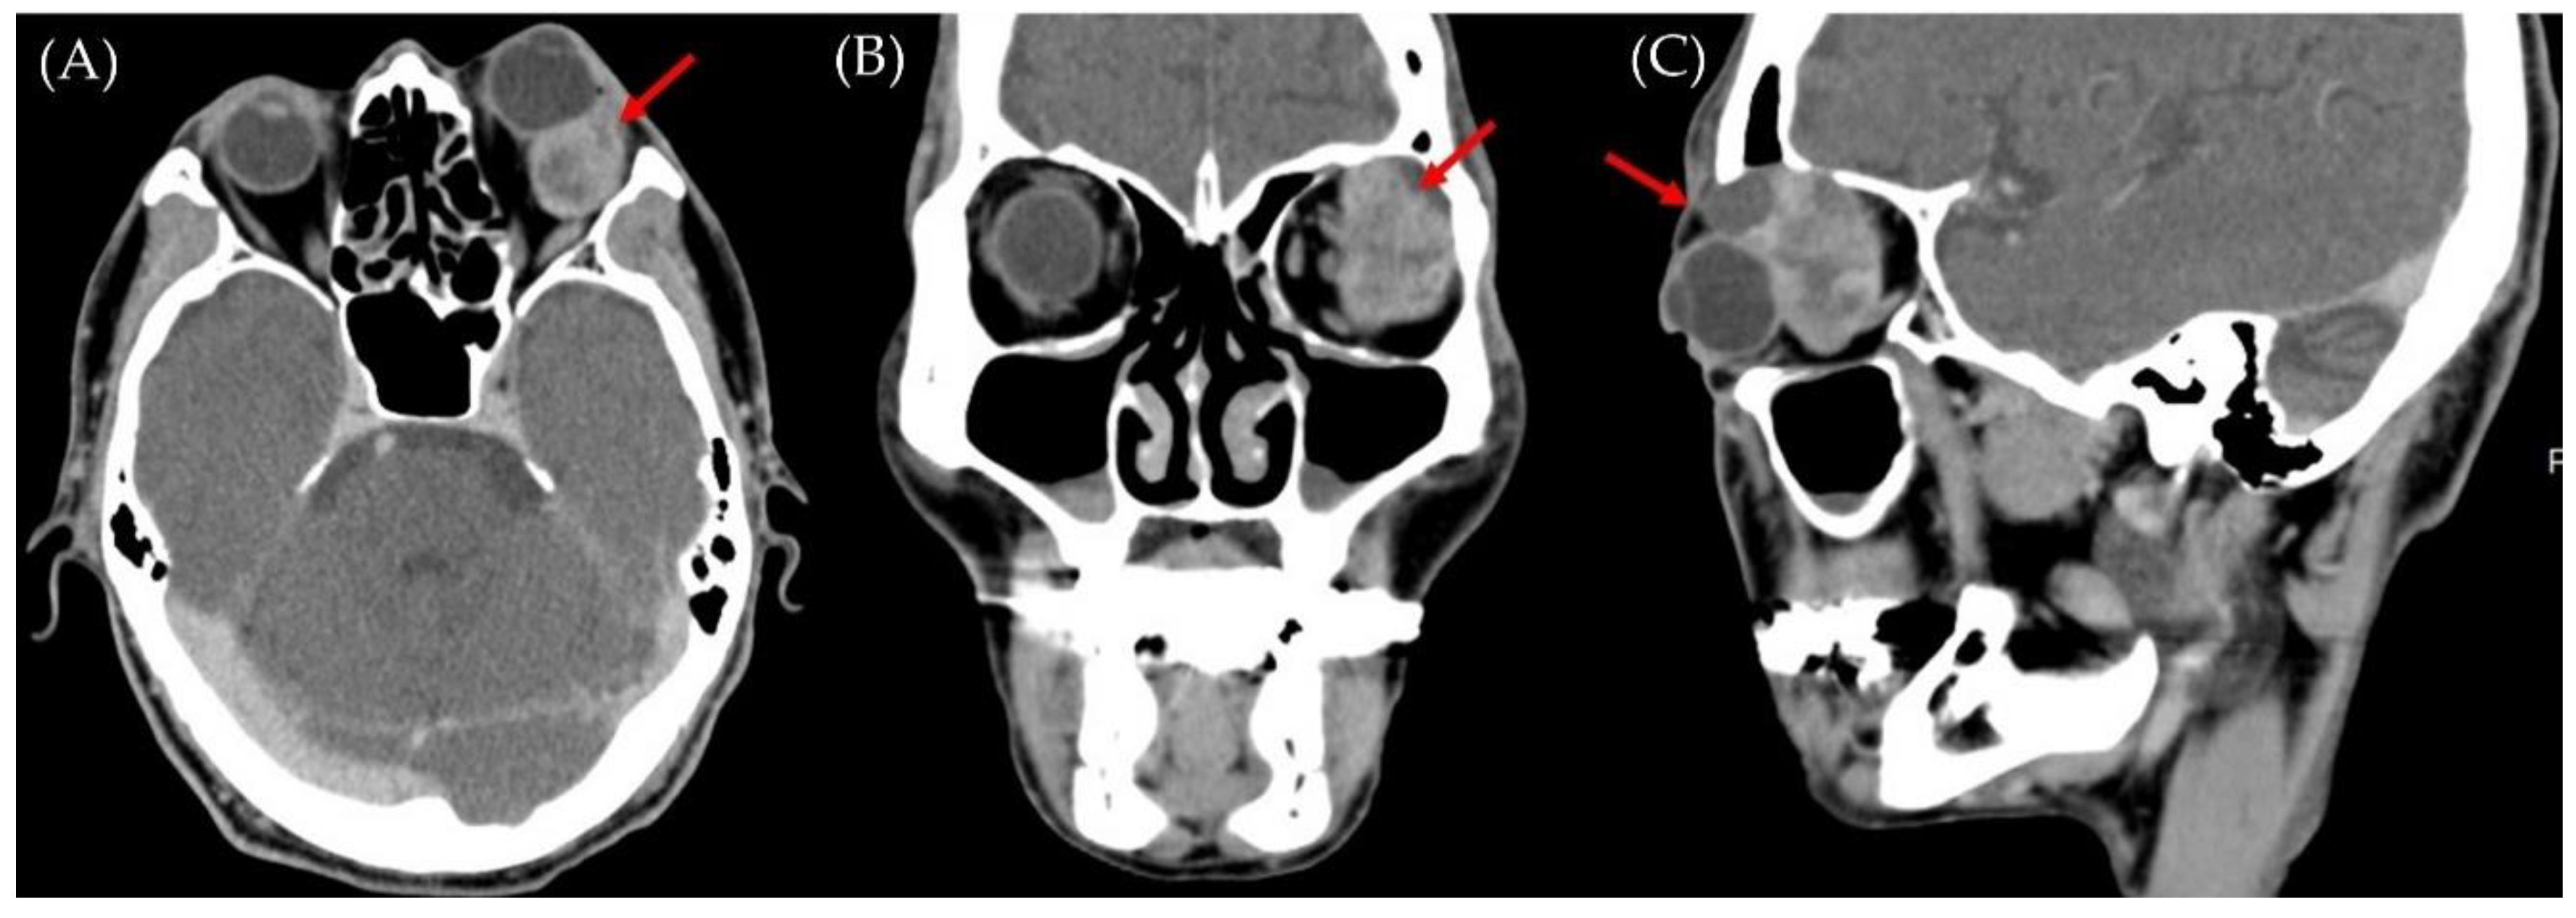

Successful Resection of Retrobulbar Carcinosarcoma without Recurrence: A Case Report

2. Case Report